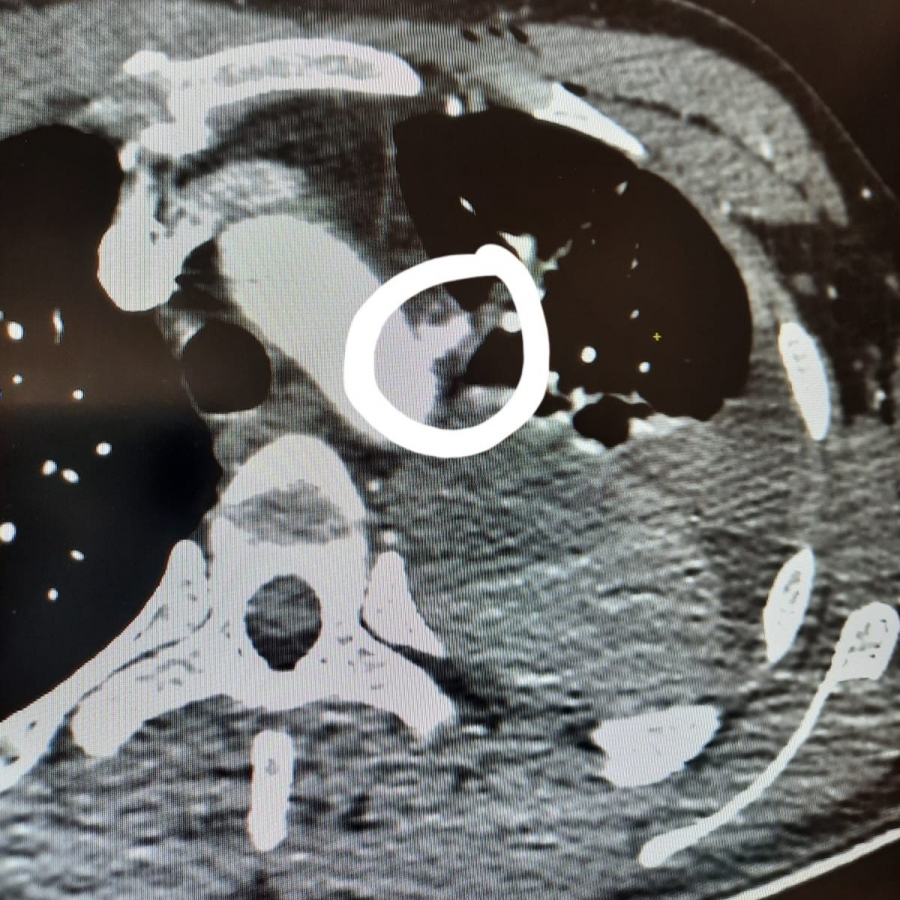

В реанимации мужчина оказался с повторным обширным гемотораксом (накопление крови в плевральной полости, резкое сокращение объема циркулирующей крови при кровопотере). К массированному кровотечению привело осколочное проникающее ранение грудной клетки. Осколок затронул аорту ниже отхождения левой подключичной артерии. С учетом такого расположения, а также угрозы развития летального кровотечения пациента немедленно транспортировали в диспансер.

Военному провели операцию по ушиванию дефекта нисходящей аорты. Команде хирургов удалось избежать искусственного кровообращения и полного рассечения грудной клетки.

«В плевральной полости было обнаружено большое количество сгустков, мы их удалили и визуализировали нисходящую аорту. На расстоянии около 1 см от левой подключичной артерии обнаружили выступающий участок измененной стенки аорты с дефектом, края которого были рыхло адгезированы (сцеплены) между собой. Выполнили ушивание дефекта, дренировали левую плевральную полость, остановили кровопотерю», - рассказал Александр Толкачев.